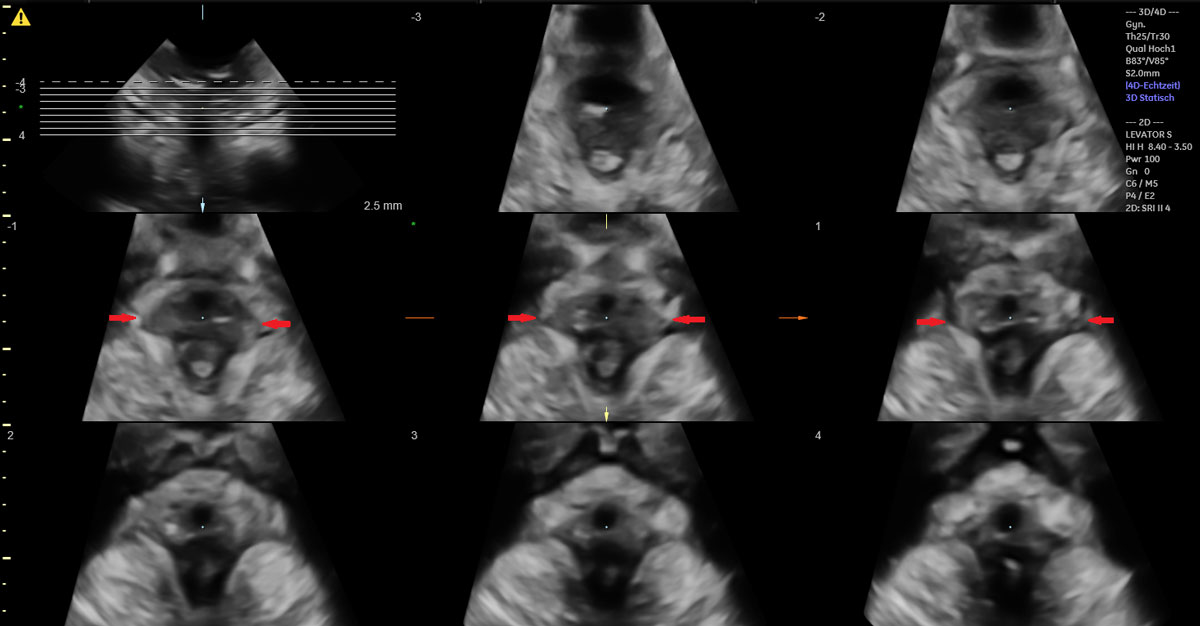

Of the 49 women with vacuum-assisted births in our cohort, 32 (65.3%) had an intact levator ani muscle, as shown in the illustration in fig. 2a and in the 3D ultrasound scan in fig. 2b. In contrast, 17 (34.7%) sustained levator ani muscle trauma, with 9 women (18.4%) having a partial levator ani muscle avulsion and 8 women (16.3%) having a complete levator ani muscle avulsion, as shown in the illustration in fig. 3a and in the 3D ultrasound scan in fig. 3b. No significant differences between the two groups were found, except for the state of their uterine contractions. Women without any levator ani muscle injury after vacuum extraction had more efficient uterine contractions compared to women with levator ani muscle trauma.

Figure 3b 3D translabial ultrasound image of a complete bilateral levator ani muscle avulsion.